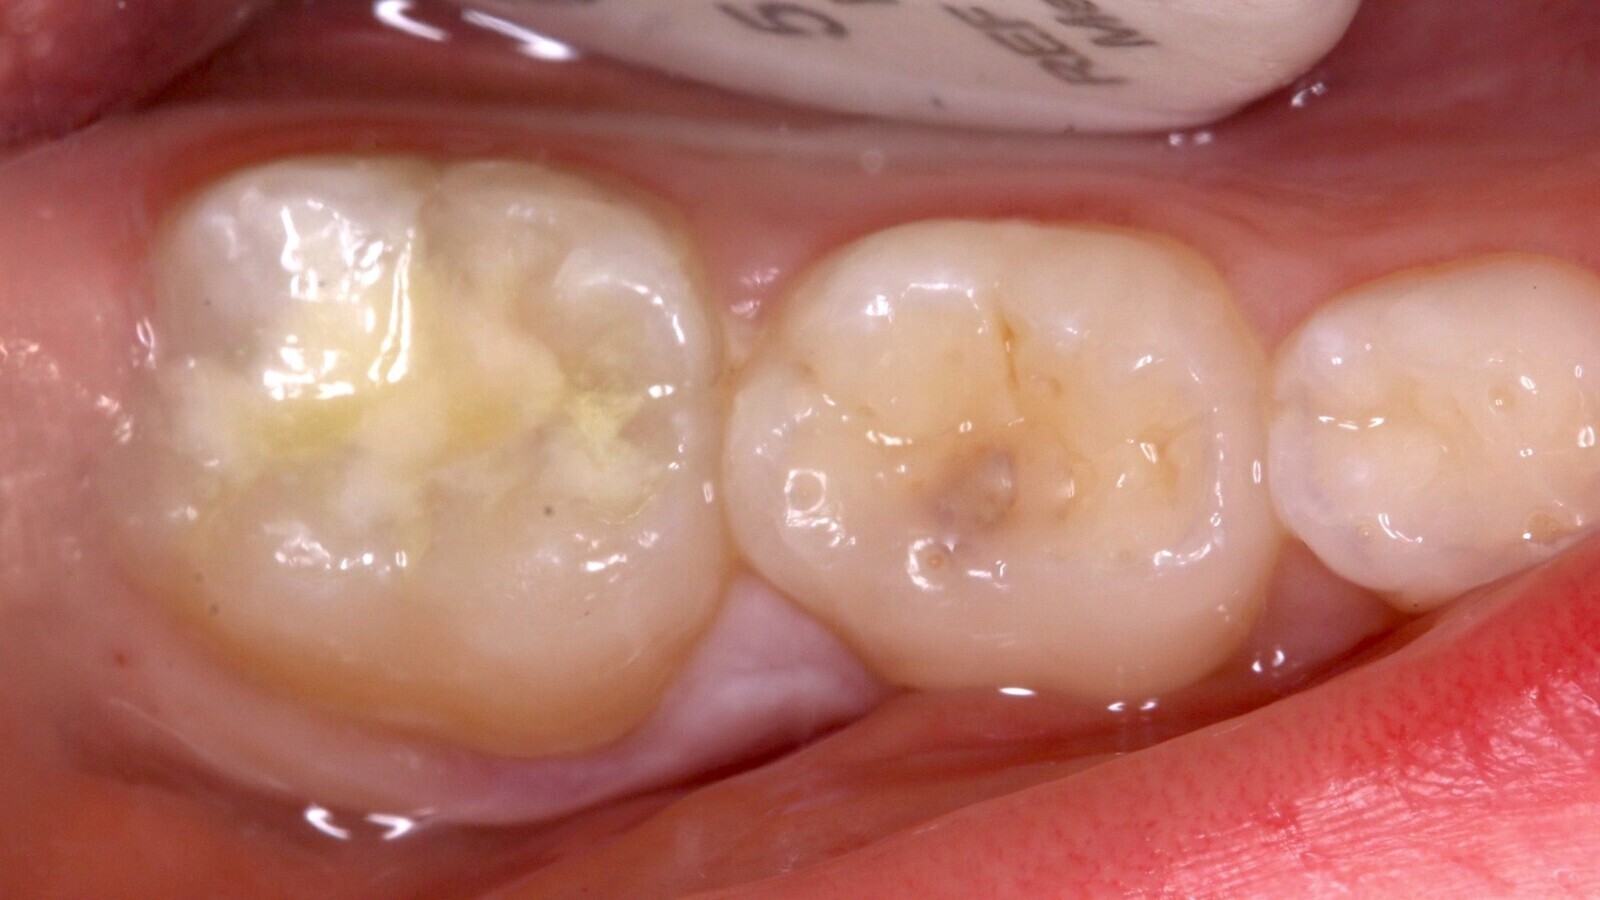

Imágenes inicial (A), radiográfica (B) y final (C) del diente 46 de una paciente de 7 años con sensibilidad dentinaria, que se restauró utilizando el material estético de fraguado rápido EQUIA Forte fil, y la resina compuesta everX Flow. Estos materiales utilizan la nueva tecnología de vidrio híbrido y actúan de forma sinérgica para formar un material más fuerte de colocación en bloque.

El material se extruye dentro la cavidad luego de realizar la mezcla durante 10 segundos y colocando la cápsula en un dispensador (Fig. 10) que permite aplicar el material desde el piso hasta los márgenes de la cavidad en un solo incremento. Inmediatamente, tras haber aplicado vaselina líquida con un pincel sobre la impresión oclusal, se procede al estampado. Posteriormente al fraguado inicial (2 - 3 minutos), se retira la copia oclusal y se eliminan los excesos que se extruyeron hacia los lados utilizando un instrumento manual (Carver, LM Arte) (Fig. 11). Se remueven los restos de vaselina y se aplica el EQUIA Forte Coat sobre la superficie del material para luego polimerizar durante 20 segundos (Fig. 12). Se realiza el control de oclusión y se da de alta a la paciente con la recomendación de evitar consumir alimentos duros por las próximas horas (Fig. 13).

Fig. 13. Se realiza el control de oclusión y se da de alta a la paciente con la recomendación de evitar consumir alimentos en las próximas horas.